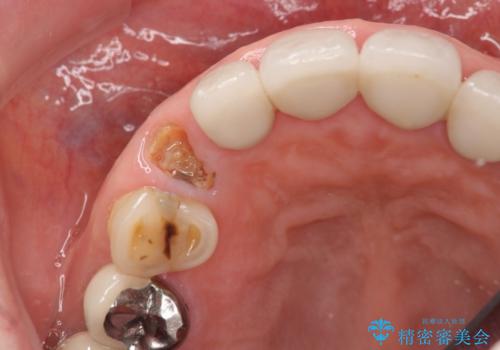

クラウン下に再発した深い虫歯 インプラントによる機能回復

- 定期検診で通院されていたところ、20年前に他院で治療した前歯のセラミック歯の下に深い虫歯が再発していることがわかりました。

ブリッジや歯の挺出を行い保存する提案も行いましたが、短期間の定期的な通院が難しくインプラントによる少ない回数での治療を希望されました。

前歯のインプラントを仕上げるには骨や歯ぐきの条件を整えることが肝要です。